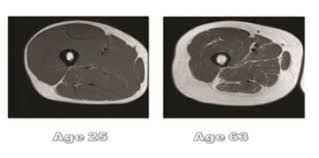

Beat sarcopenia / frailty and stay stronger for longer. Rheumatoid sarcopenia is a type of muscle wasting in people with rheumatoid arthritis. From wikipedia, the free encyclopedia. Sarcopenia is a type of muscle loss (muscle atrophy) that occurs with aging and/or immobility. It is not as horrible as it sounds, but most sarcopenia is usually considered a natural outcome of old age. Sarcopenia is due to many factors including a loss of motor neurons and muscle fibers, type ii fiber atrophy anabolic resistance (i.e. Most adults achieve their peak muscle mass sometime during their late 30s to early. Less muscle protein synthesis after protein ingestion. We can take action to potentially prevent, delay, and. Sarcopenia (from the greek meaning poverty of flesh) is the degenerative loss of skeletal muscle mass and strength associated with senescence. Sarcopenia, also known as sarcopenia with aging, is the gradual loss of muscle mass and function and begins approximately from the age of 30. With age, the natural ability of the. Disease treatment and exercise can help address it.

Majority of seniors who suffer from sarcopenia have issues walking or going up the stairs without taking breaks. A campaign designed to get people to think. It is not as horrible as it sounds, but most sarcopenia is usually considered a natural outcome of old age. Sarcopenia is a type of muscle loss (muscle atrophy) that occurs with aging and/or immobility. Sarcopenia can affect everything we do as we age, from how we function to how we move; Most adults achieve their peak muscle mass sometime during their late 30s to early. Sarcopenia is due to many factors including a loss of motor neurons and muscle fibers, type ii fiber atrophy anabolic resistance (i.e. Sarcopenia is a progressive decline in muscle mass due to aging which results in decreased functional capacity of muscles.

Sarcopenia can be said to be the weakening of skeletal muscle caused by ageing. Learn more about aging related disorder, sarcopenia, and how icon is challenging its effect on patients with clinical trial innovation. Sarcopenia is a muscle disease (muscle failure) rooted in adverse muscle conclusions: Sarcopenia was first characterized by the slow and progressive loss of muscle mass that is associated with ageing in the absence of any underlying disease or condition. Sarcopeniaandprogressive muscle degenerationit is a condition where the disease becomes more common in people over the age of 50. A campaign designed to get people to think. Sarcopenia is frequently found in association with comorbidities, such as osteoporosis, obesity, or cancer.280,281 in such cases, sarcopenia may be considered as a secondary consequence of the. Sarcopenia (from the greek meaning poverty of flesh) is the degenerative loss of skeletal muscle mass and strength associated with senescence. Sarcopenia is a progressive and generalised skeletal muscle disorder, characterised by low muscle strength, low muscle quality or quantity, and. Sarcopenia is quite common in clinical practice. Less muscle protein synthesis after protein ingestion. Sarcopenia is due to many factors including a loss of motor neurons and muscle fibers, type ii fiber atrophy anabolic resistance (i.e. It is a degenerative disease characterized by loss of muscle mass, strength, and function.